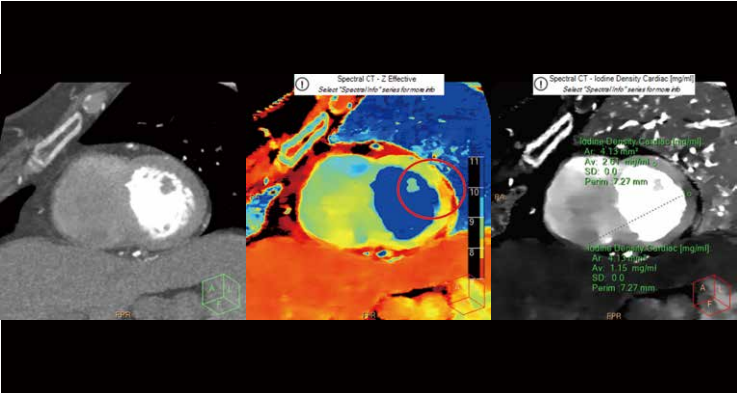

在心脏诊断方面,一次扫描条件下,该CT可显示冠状动脉的解剖结构、冠状动脉斑块的物质成分和心肌血液灌注信息,还可判断心肌活性、支架再狭窄、斑块定量定性分析、ECV定量评估等,为心肌疾病和结构性心脏病的同步诊断带来了多参数评估体系,是目前唯一实现临床常规化心脏能量精准成像的设备。